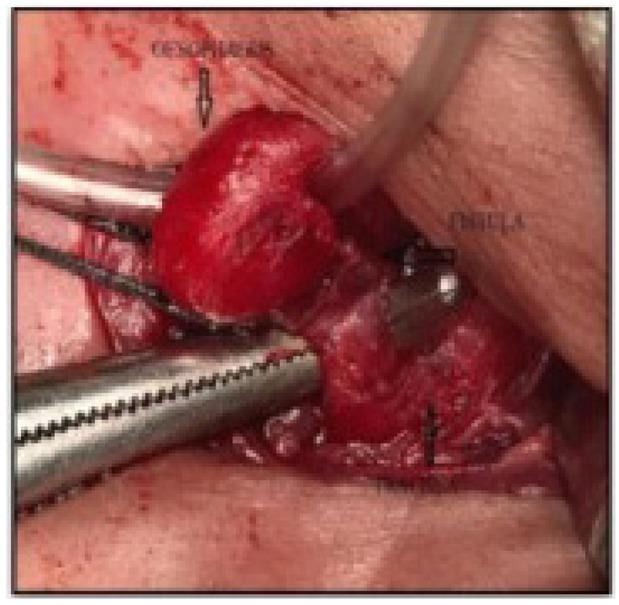

Figure 4